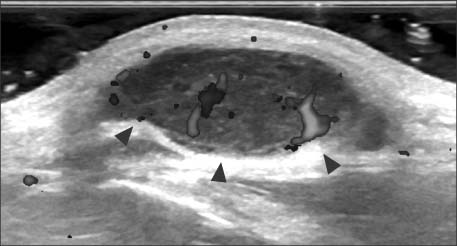

Fig. 2.

Ultrasonographic image showing a hypoechoic lobulated mass, with 2.2×2.4×0.8 cm size and inner vascularity (arrowheads).

Fig. 2. Ultrasonographic image showing a hypoechoic lobulated mass, with 2.2×2.4×0.8 cm size and inner vascularity (arrowheads).